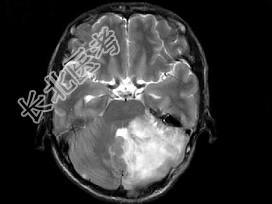

- 单项选择题男,41岁, 左枕部疼痛,右侧肢体乏力, 并渐进性加重半个月,右侧肢体乏力, 行走不稳,根据所提供图像, 最可能的诊断是 ( )

A、(小脑)血管母细胞瘤

B、(小脑)髓母细胞瘤

C、(小脑)炎性肉芽肿

D、(小脑)转移瘤

E、(小脑)星形胶质细胞瘤Ⅰ~Ⅱ级